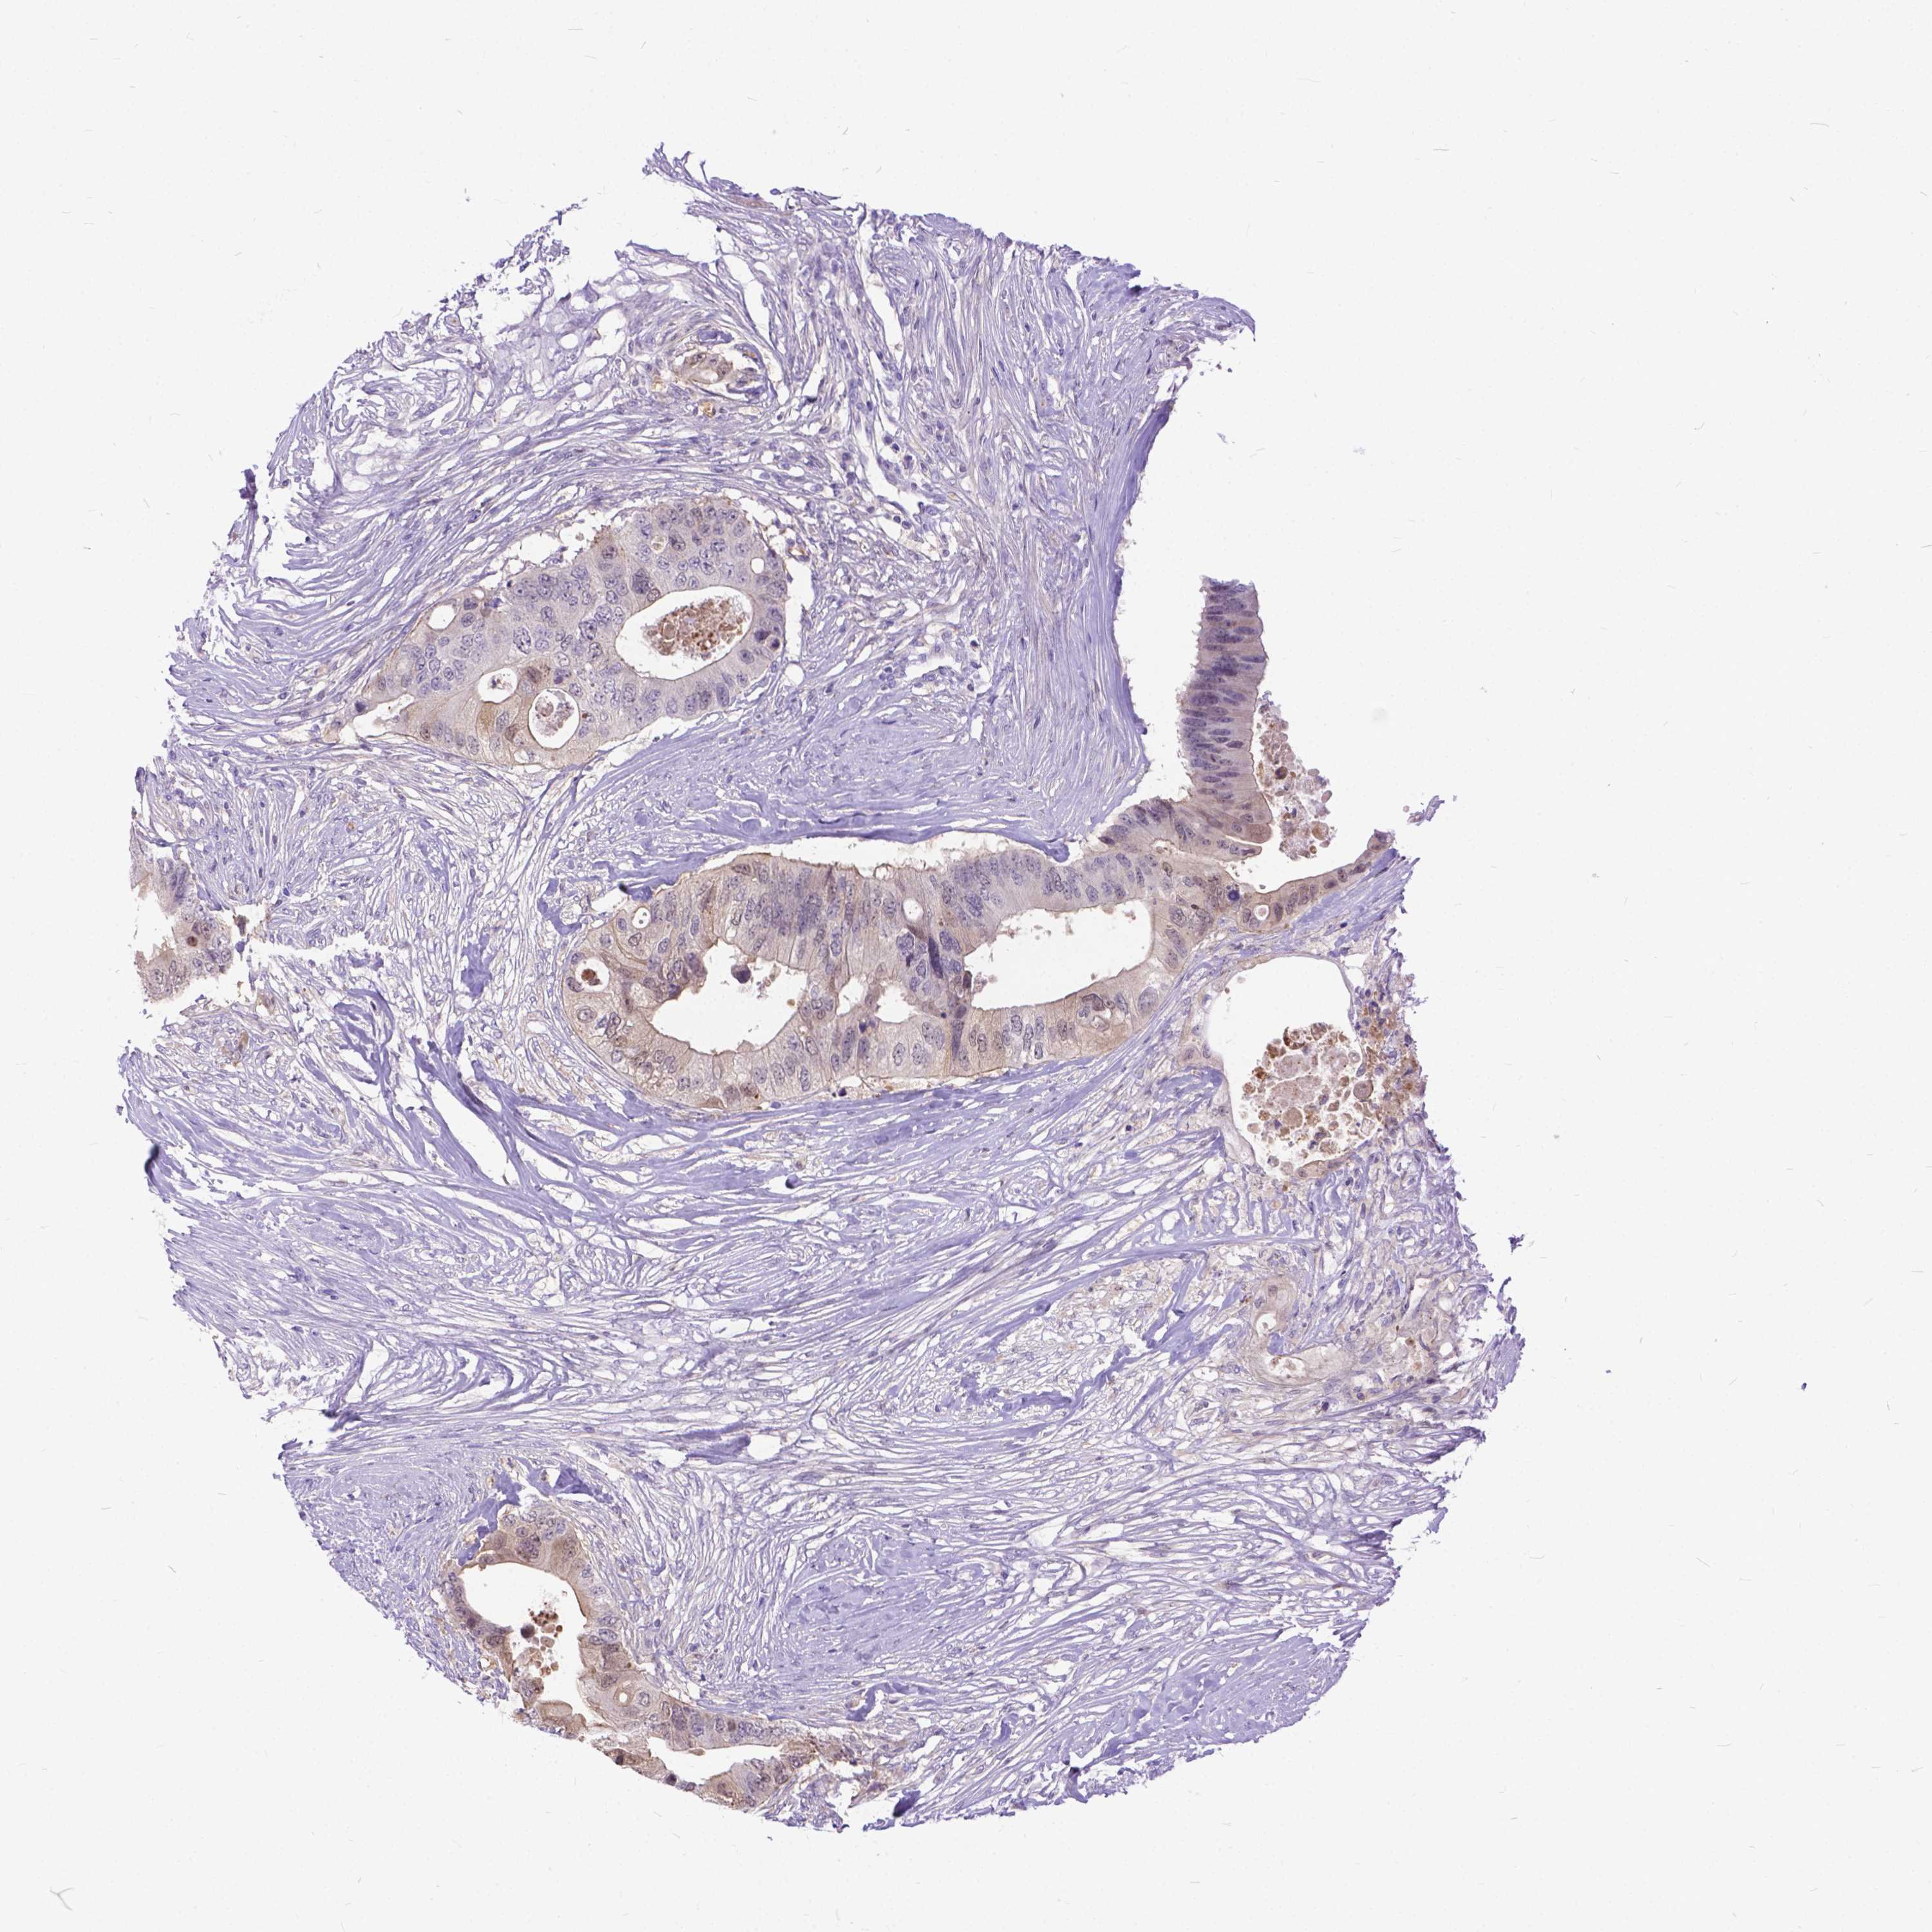

CANCER COLORECTAL CANCER Show tissue menu

Colorectal cancer

Human cancer

Colon adenocarcinoma